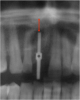

Fig 4. Radiographic imaging was used to establish vertical control of implant placement and ensure the presence of sufficient bone on either side of the implant.

Figure 4

Radiographic examination of the site for implant placement is essential to determine the presence of adequate space for the implant and subsequent restoration (eg, central incisor) and to assess soft-tissue architecture.1,2 Computed tomography (CT) images and panoramic radiographs (eg, panorex) have been used in implant dentistry to help identify structures critical for implant placement and establish the safe, short distance for implant placement (ie, vertical control of implant placement) using a pilot drill (Figure 4).5